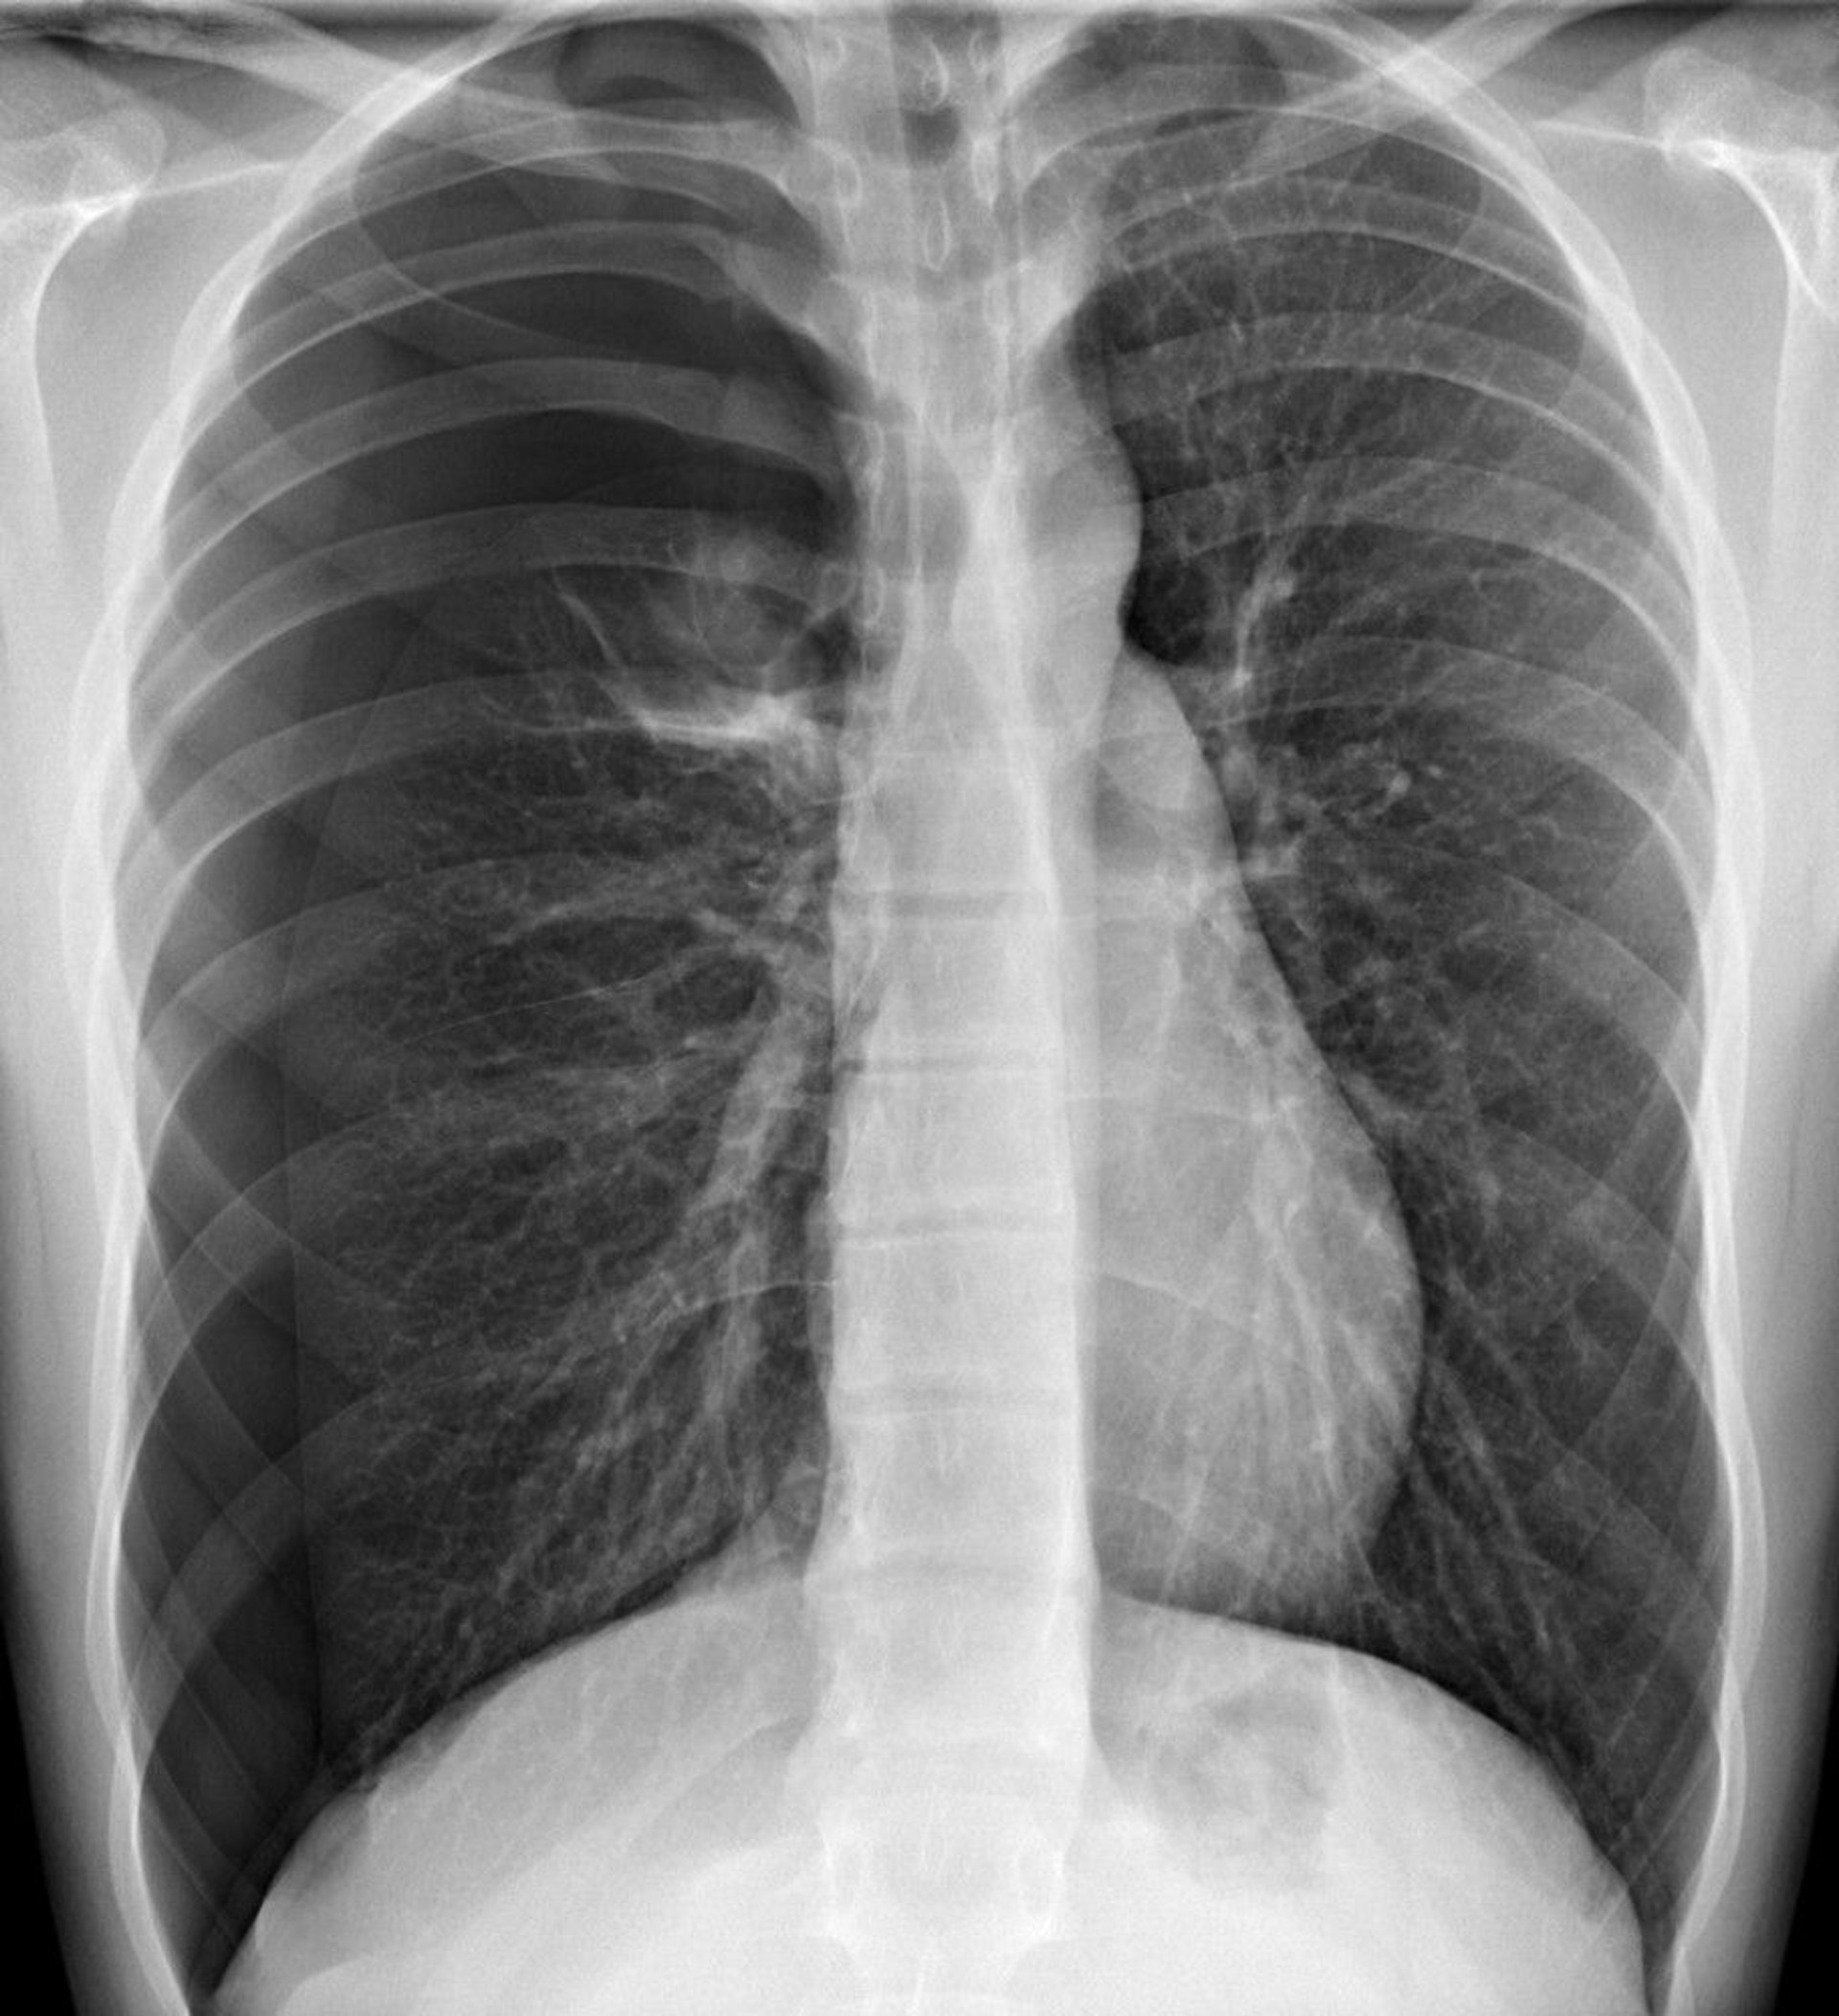

Tension Pneumothorax

In this image, a pneumothorax is visible in the right hemithorax, where, in the periphery, there are no lung markings. A shift of the heart and mediastinum toward the left side can cause tension pneumothorax physiology. Tension pneumothorax, however, should be diagnosed clinically and not await radiographic confirmation.

DU CANE MEDICAL IMAGING LTD/SCIENCE PHOTO LIBRARY